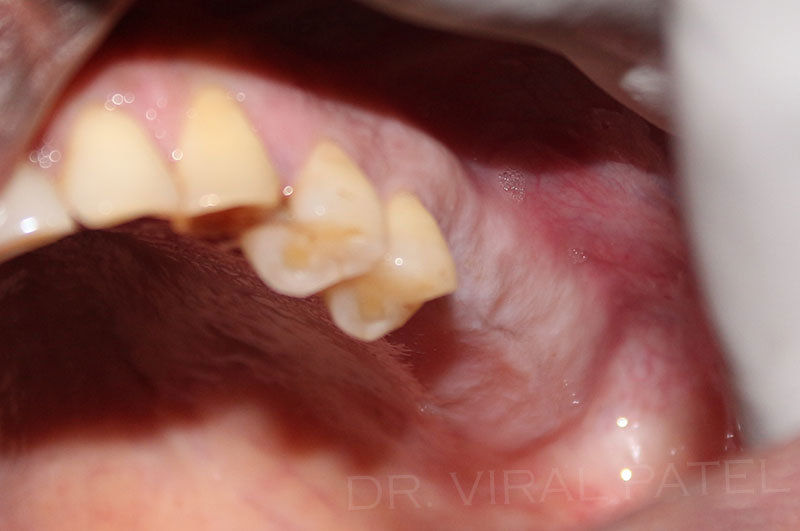

Dr Patel Also use single stage stitchless or flapless technique to place dental implants which is only one time procedure.

Today, advanced implant systems and the use of Cone Beam CT scans allow experienced dental professionals to insert the implants, and immediately place the new teeth on the implant.